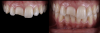

When dealing with complex tooth fractures and extensive restorations, some practitioners choose to perform traditional indirect restoration procedures, starting with a wax-up and a silicone index, and in a second appointment the practitioner would layer the restorative material. A third appointment might even be required. However, sometimes such treatments, such as in Figure 1, can be performed with simpler and faster techniques such as direct restoration. This type of restoration requires specific clinician skills of managing the composite, anatomy, and textures, which sometimes might lead the dentist not to perform it. While direct procedures are highly dependent on the dentist, indirect restorations are highly dependent on the laboratory technician.

Fig. 1  Anterior facture.

Figure 1